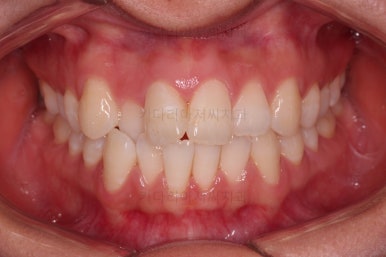

부산교정잘하는치과 초진 시 입안의 모습입ㄴ디ㅏ.

맞물림은 크게 나쁜 편은 아니었고요.

앞니 쪽이 위아래가 다 삐뚤고, 위에 작은 앞니 하나가 거꾸로 물리는 상태였습니다.

거꾸로 물리는 상황에서 특히 아래 앞니는 점점 잇몸이 꺼지는 증상이 생기면서 장기적인 치아의 수명에 영향을 주게 됩니다.